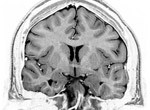

MRI of the human brainUniversity of Utah (U of U) medical researchers have made an important step in diagnosing autism through using MRI, an advance that eventually could help health care providers identify the problem much earlier in children and lead to improved treatment and outcomes for those with the disorder. The study is published in October 15, 2010 edition of Cerebral Cortex online.

Researchers led by neuroradiologist Jeffery S. Anderson, M.D., Ph.D., U of U assistant professor of radiology, used MRI to identify areas where the left and right hemispheres of the brains of people with autism do not properly communicate with one another. Those areas are in “hot spots” associated with functions such as motor skills, attention, facial recognition, and social functioning – behaviors that are abnormal in autism. MRI’s of people without the disorder did not show the same deficits.

Other than increased brain size in young children with autism, there are no major structural differences between the brains of people with autism and those who do not have the disorder that can be used to diagnose autism on a routine brain MRI. It has been long believed that more profound differences could be discovered by studying how regions in the brain communicate with each other.